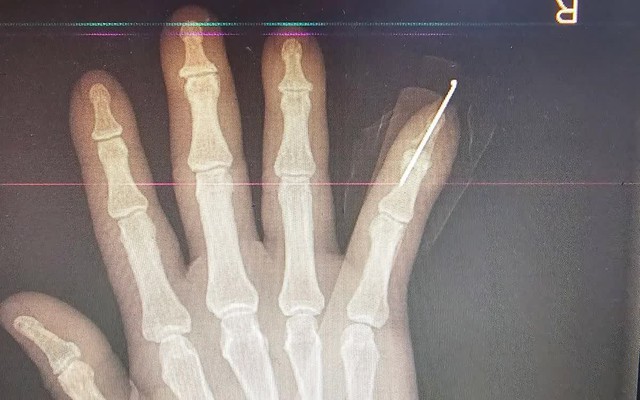

Bệnh nhân là nam giới, 63 tuổi, bị tôn cắt trong lúc làm việc. Khi nhập viện, bệnh nhân trong tình trạng đứt lìa hoàn toàn đốt 3 ngón V bàn tay phải, vết thương sắc gọn, nguy cơ cao mất chức năng bàn tay nếu không được can thiệp kịp thời. Ngay sau khi tiếp nhận, các bác sĩ nhanh chóng đánh giá tổn thương và chỉ định phẫu thuật vi phẫu cấp cứu.

Ekip phẫu thuật đã tiến hành nối xương, gân, mạch máu và thần kinh bằng kỹ thuật vi phẫu chuyên sâu. Ca mổ diễn ra thuận lợi, ngón tay được tái lập tuần hoàn tốt. Sau phẫu thuật, bệnh nhân tiếp tục được theo dõi sát và tập phục hồi chức năng nhằm tối ưu khả năng vận động của bàn tay.